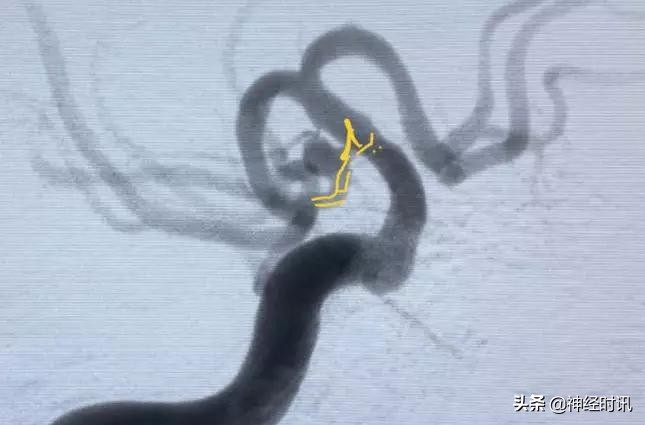

病例1是一个破裂的后交通动脉瘤,后交通动脉粗大,是胚胎大脑后动脉,必须保留;该动脉瘤并不和常见的后交通动脉瘤一样颈部接近颈内动脉主干,而是完全起于后交通动脉,而且后交通的起始部有狭窄,在动脉瘤颈部略有成角。

点击图片可查看大图详情